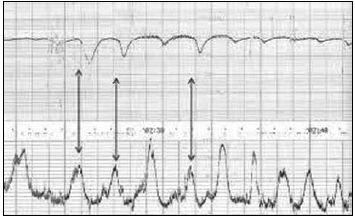

No mesmo momento do toque, foi realizada a seguinte cardiotocografia.

Enunciado 4100126-2

Com base nesse traçado, quais são a classificação e a conduta?